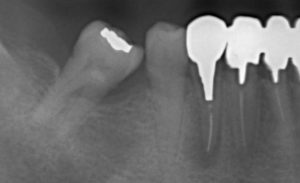

上下ともに当院初診時のレントゲンです。

下の写真は奥歯のブリッジ治療が終わり、ファイルの折れ込みや歯肉の腫れがある歯を治療するため銀歯とメタルコア(金属の芯)を除去したところです。